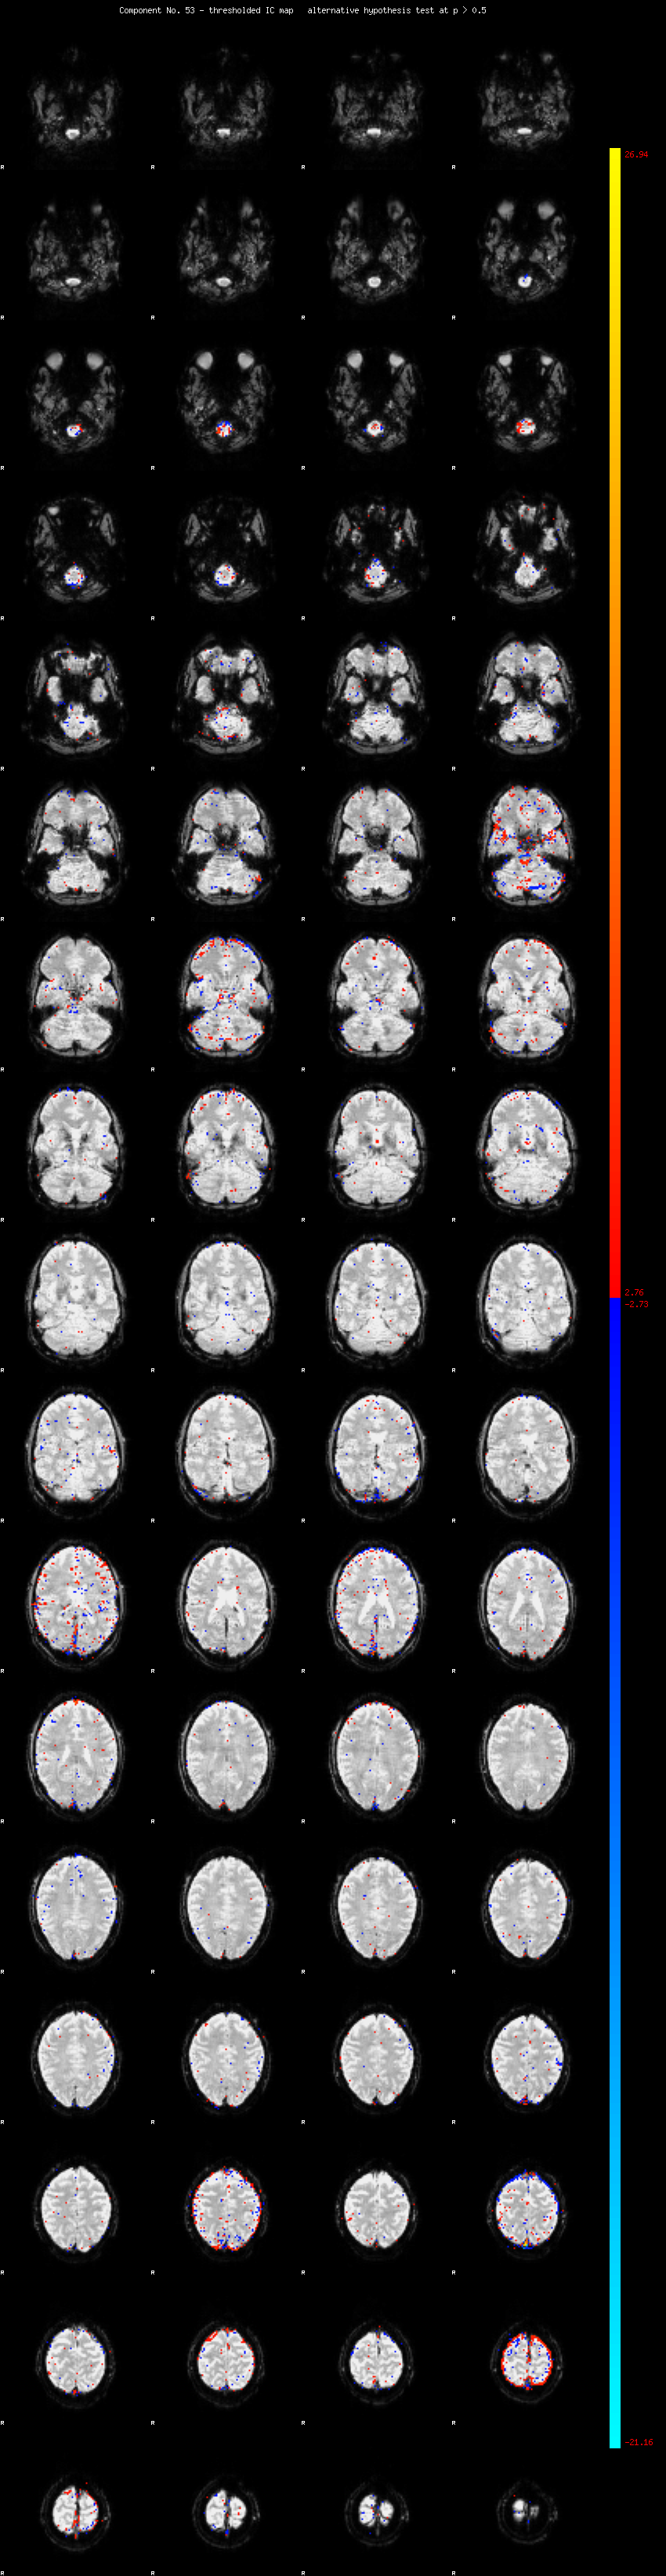

MELODIC Component 53

0.93 % of explained variance;     0.61 % of total variance